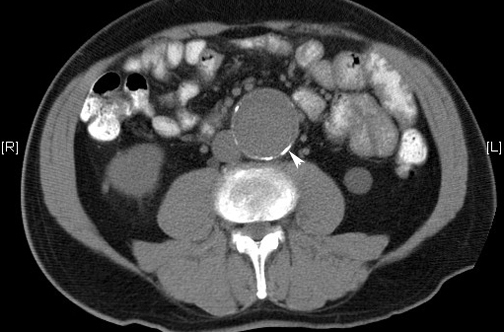

Aneurismas de aorta abdominal: más cirugías y menos mortalidad en EEUU